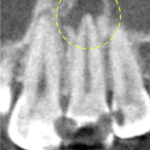

術前のレントゲン・CT画像にて、根の先に大きな黒い影が認められました。

歯の神経の状態の検査からも、神経の反応はなく、歯髄壊死(神経が死んでしまっている状態)と診断しました。

レントゲン写真にて、根の先の黒い影(骨の吸収像)の縮小傾向が認められました。

わずかにまだ黒い影が残っているため、さらに追加で6ヶ月、術後12ヶ月まで経過をみることになりました。